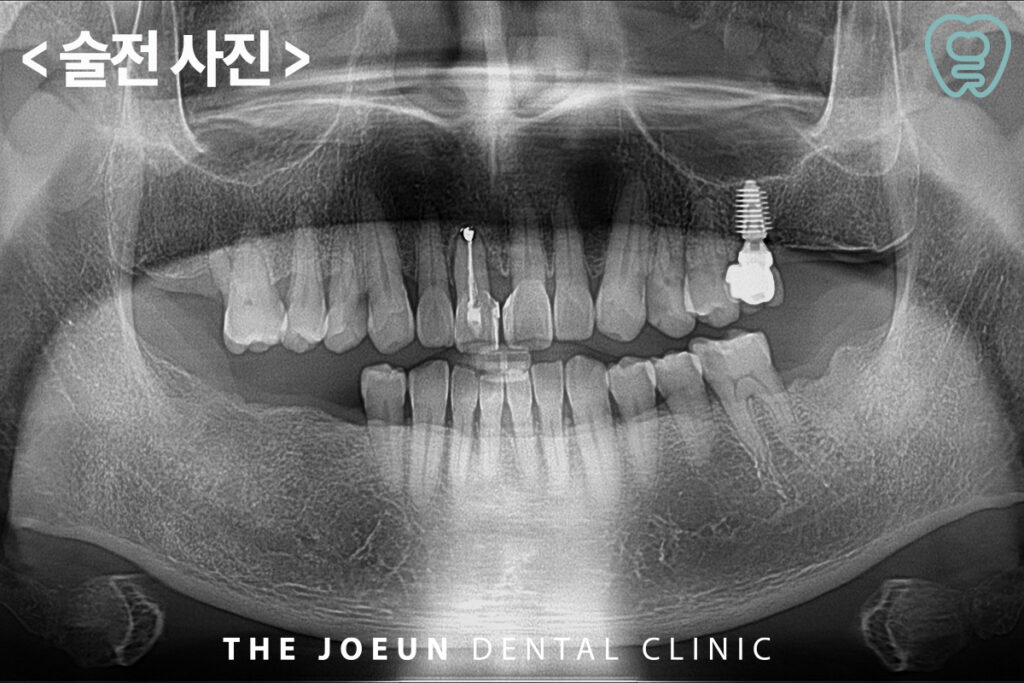

오늘은 심한 치주염으로 인해 다수 치아 발치 후 즉시 임플란트를 진행하신 환자분을 소개해 드리려고 합니다.

환자분께서는 구강 내 어금니 부위 상실하신 곳이 전반적으로 관찰되고 있었고 구강 위생 관리가 제대로 이루어지지 않아 심한 치주염이 진행되고 있는 상태였습니다. 따라서 치주염이 심한 치아는 발치하고 위,아래 상실하신 어금니 부위는 임플란트를 통해 수복을 진행하기로 계획하였습니다.